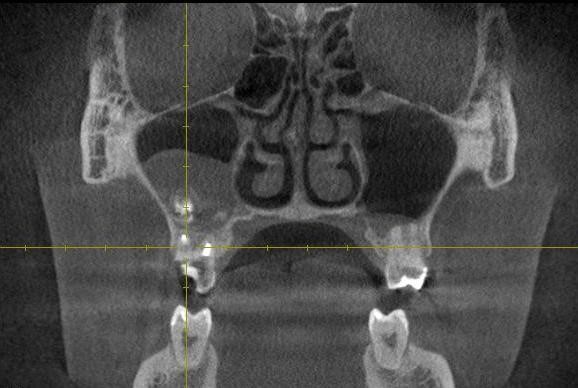

Для постановки диагноза «синусит» проводят рентгенографию пазух. На снимках видно затемнение пазух, его интенсивность различна. Для подтверждения диагноза «одонтогенный гайморит» необходимо найти источник одонтогенной инфекции, то есть причинный зуб. Проводят рентгенологическое исследование верхних жевательных зубов, при котором определяются признаки апикального периодонтита причинного зуба.

Однако диагноз можно считать подтвержденным только при совокупности клинических и рентгенологических признаков.

Диагноз ставится на основании клинических и рентгенологических симптомов, данных анамнеза. Лучше всего провести компьютерную томографию, на которой будет видна степень пневматизации пазух, рентгенологические изменения на верхушках причинных зубов, соотношение их корней с пазухой.